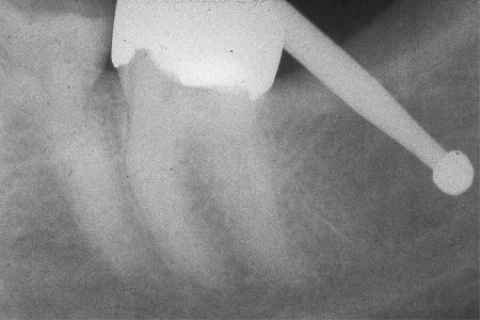

[ Image Source: http://www.maxillofacialcenter.com/NICOxray/NICOxr2.html

The text from the website reads: "A rounded radiolucency posterior to the molar is so subtle that it is barely visible. It was a dry, hollow space or cavitation. The bur stops at the base of the lesion, which is as yet undisturbed except for the cortical window made to gain access."